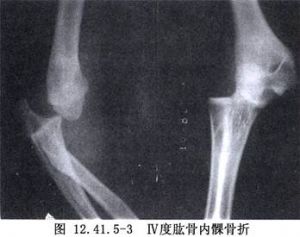

肱骨内髁骨折切开复位术用于肱骨内髁骨折的治疗。肱骨内髁骨折罕见,占儿童肘部骨折1%以下。多见于8~14岁儿童(图12.41.5-1~12.41.5-3)。